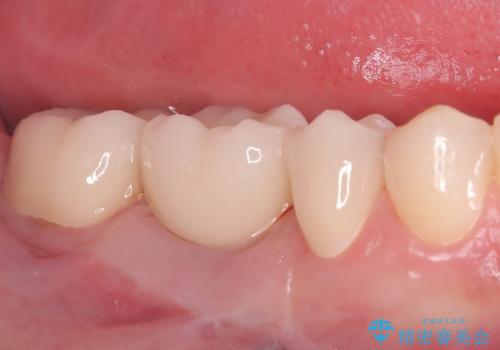

繰り返すプラスチックの欠けを解消。広範囲の修復に適したセラミッククラウン

担当医 河口智英